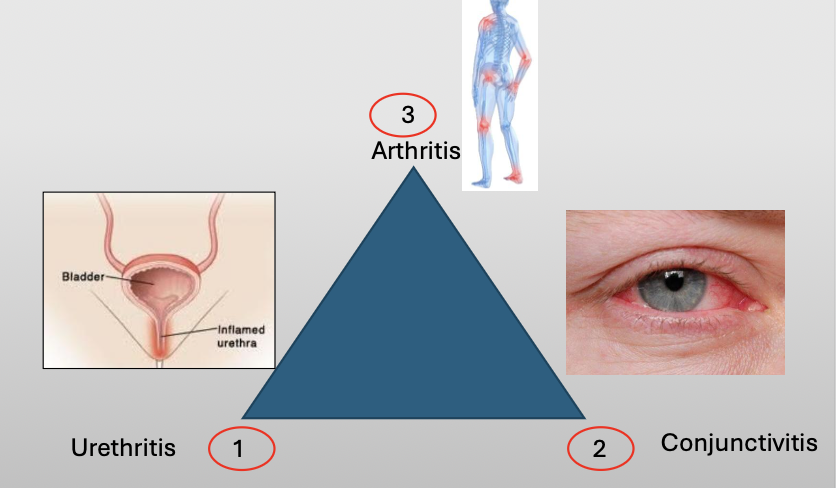

What is another name for reactive arthritis

Reiter Syndrome

What is Reiter Syndrome?

A chronic disease that classically compromises a triad of three featuers:

Urethritis

Conjunctivitis

Arthritis

What is the cause of Reiter Syndrome?

Unknown, 10% have HLA-B27

Oral lesions are 20% (nonspecific)

NSAID/AB if infection/steroids

What demographic does Reiter Syndrome show up in?

M:F (9:1)